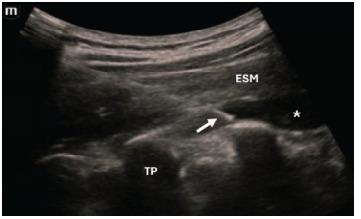

超声引导下竖脊肌平面阻滞用于急诊科胰腺癌和肝胆恶性肿瘤突破性疼痛:病例系列

Ultrasound-Guided Erector Spinae Plane Block for Breakthrough Pancreatic and Hepatobiliary Malignancy Pain in the Emergency Department: A Case Series.

Breakthrough pain is frequently experienced by patients with gastrointestinal malignancies and is a common reason for presenting to the emergency department (ED). After ruling out acute pathology, ED management typically consists of intravenous opioids, although high doses of opioids can be associated with potentially severe adverse events and complications in certain high-risk populations. Regional anesthesia strategies, such as the erector spinae plane block (ESPB), have been shown to be effective for several etiologies of non-malignant visceral abdominal pain. In this case series we sought to evaluate whether the ESPB can be effective for ED patients with breakthrough pancreatic and hepatobiliary cancer pain.

Three patients with breakthrough hepatopancreatobiliary cancer pain underwent successful ESPBs performed by an emergency physician in the ED. All patients reported considerable reduction in their pain. Two patients with cancer of the pancreatic head reported complete pain relief and were able to be discharged from the ED. The third patient with metastatic colorectal cancer involving the hepatobiliary system was admitted for further medical workup, although he did not require any additional analgesics for nearly 13 hours after the block.

The erector spinae plane block appears to be a safe and effective strategy for managing breakthrough pain related to pancreatic and hepatobiliary malignancy in the ED.